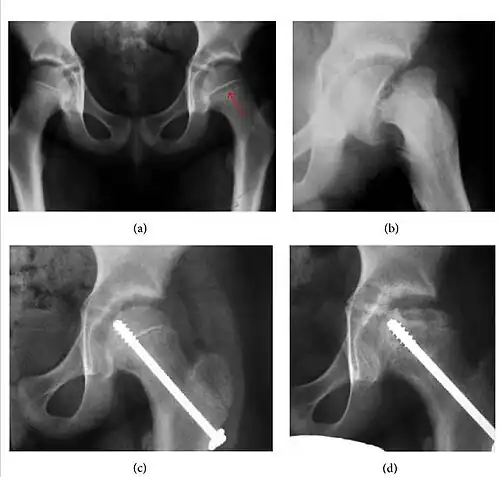

- Slipped capital femoral epiphyses (SCFE)

Slipped capital femoral epiphyses (SCFE) usually affect 11- to 14-year-old adolescents (Figure 4). Radiographs may show widening and irregularity of the physis and posterior inferior displacement of the capital femoral epiphysis. On the AP view Klein’s line, tangent to the lateral aspect of the femoral neck, does not intersect the femoral head indicating that it is displaced. SCFE may compromise the blood supply to the femoral head and cause avascular necrosis, mainly when there is instability between the fragments.[1]

-

Figure 4: (a) X-ray of a 10-year-old child with left hip pain. It was considered normal at emergency despite the widening of the left physis (arrow). Two weeks later epiphysiolysis was evident (b). Despite appropriate surgical reduction (c) osteonecrosis developed and femoral head collapsed 1 month later (d).[1]